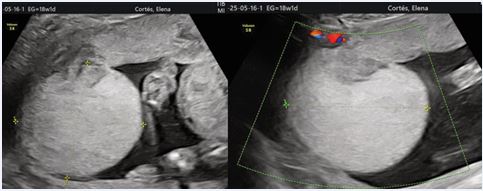

A 33-year-old primigravida was referred to our maternal–fetal medicine unit at 18 weeks’ gestation due to a suspected placental mass. The pregnancy had been uncomplicated, with no relevant medical or obstetric history. Ultrasound examination revealed a well-defined, hypoechoic, vascular placental mass measuring 5.9 × 6.5 cm, located near the umbilical cord insertion on the fetal surface (Figure 1).

Figure 1: Prenatal ultrasound image demonstrating a well-defined, hypoechoic placental mass located on the fetal surface near the umbilical cord insertion. Colour Doppler imaging shows abundant low-resistance arterial blood flow within the lesion, consistent with a giant placental chorioangioma.

Colour Doppler imaging demonstrated abundant low-resistance arterial flow, consistent with a diagnosis of placental chorioangioma. Fetal biometry, Doppler studies—including middle cerebral artery peak systolic velocity (MCA-PSV)—and amniotic fluid volume were within normal limits. Serial ultrasound examinations were performed every two weeks. The lesion remained stable in size, and no evidence of fetal anaemia, hydrops fetalis, or growth restriction was observed. Maternal condition remained stable throughout pregnancy. At 38 weeks’ gestation, an elective cesarean section was performed due to breech presentation and the vascular nature of the tumour, with concern for potential intrapartum complications. A healthy female neonate weighing 3070 g was delivered, with Apgar scores of 9 and 10 at 1 and 5 minutes, respectively. Gross examination of the placenta revealed an 8.0 × 6.8 cm vascular mass on the fetal surface (Figure 2).